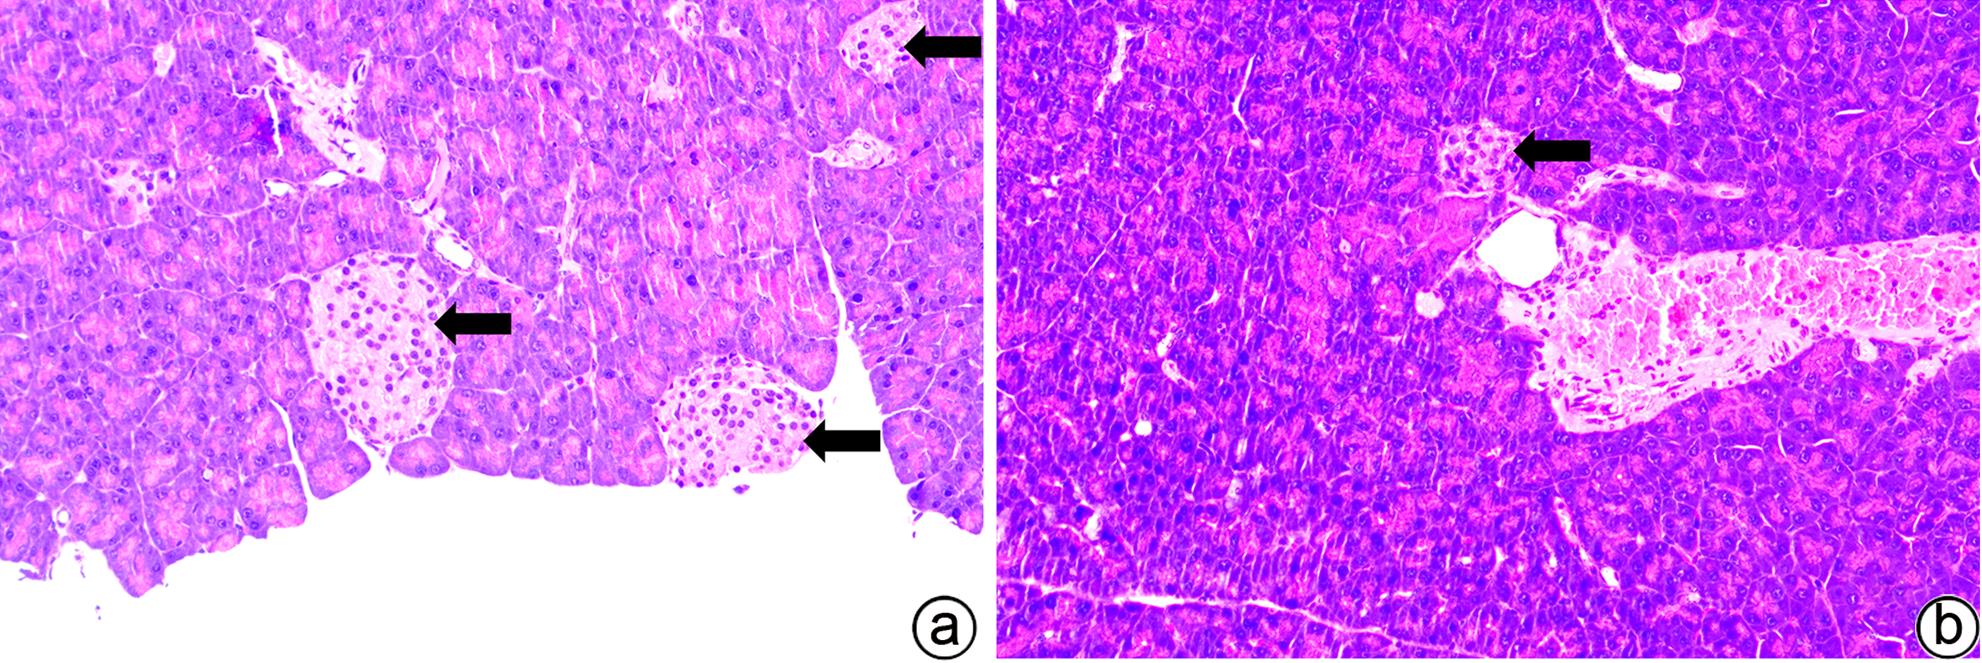

目的 建立可动态观察成瘤过程并进行体内研究的2型糖尿病(T2DM)胰腺癌裸鼠模型。 方法 首先,通过慢病毒载体GV260转染人胰腺癌细胞(PANC-1细胞)构建能稳定表达萤火虫荧光素酶的胰腺癌细胞株(PANC-1-Luc细胞)。然后,将36只SPF级裸鼠随机分为对照组(n=12,血糖正常的胰腺癌裸鼠)和模型组(n=24,T2DM胰腺癌裸鼠)。对照组:先给予繁殖饲料喂养,之后将PANC-1-Luc细胞异位种植于裸鼠皮下;模型组:先给予高脂饲料喂养联合腹腔注射1% STZ,之后将PANC-1-Luc细胞异位种植于裸鼠皮下。用荧光活体成像系统和人工测量法同步动态监测2组裸鼠胰腺癌生长情况,绘制肿瘤生长曲线、分析荧光值与肿瘤体积的关系。显微镜下观察裸鼠皮下肿瘤及胰岛,验证造模是否成功;同时,通过免疫组化检测肿瘤组织Ki-67的表达来分析高血糖对裸鼠胰腺癌生长的影响。正态分布计量资料组间比较采用成组t检验,非正态分布计量资料组间比较采用Mann-Whitney U检验。 结果 确定PANC-1细胞慢病毒载体稳定转染的最佳病毒滴度为5×107 TU/mL,用嘌呤霉素筛选的最佳浓度为20 μg/mL、最佳筛选时间为9天;PANC-1-Luc细胞的荧光值与细胞数量呈线性正相关,线性方程为y=42.56x-42 504(r=0.977,P=0.004)。T2DM裸鼠模型血糖值为23.05(19.25~26.40)mmol/L,且每只裸鼠的血糖均高于11.1 mmol/L,与对照组裸鼠血糖值[6.15(5.20~7.30)mmol/L]相比,差异有统计学意义(Z=-8.45,P<0.001)。与对照组相比,模型组胰腺组织内胰岛数量减少、体积减小、形状不规则、边界模糊,同时移植瘤病理学检查确认镜下为胰腺癌组织,可判定T2DM裸鼠胰腺癌模型造模成功。模型组皮下肿瘤大小与荧光值呈线性正相关,线性方程为y=232 348 691x-8 258 608(r=0.911,P=0.031);模型组移植瘤Ki-67免疫组化阳性率显著高于对照组[(50.333±7.808)% vs (15.917±4.055)%,t=13.55,P<0.001],说明模型组肿瘤增殖较快。 结论 本研究所构建的T2DM裸鼠胰腺癌模型可模拟T2DM背景下胰腺癌发生、发展的病理过程,动态观察高血糖对体内胰腺癌细胞生长的影响,从而为T2DM背景下胰腺癌发生、发展的体内研究提供新的实验载体。 Abstract:Objective To establish a nude mouse model of type 2 diabetes mellitus (T2DM) and pancreatic cancer that allows dynamic observation of tumor formation process and facilitates in vivo research. Methods At first, human pancreatic cancer PANC-1 cells were transfected with lentiviral vector GV260 to construct the pancreatic cancer cell line PANC-1-Luc with stable expression of firefly luciferase. Then, 36 specific pathogen-free nude mice were randomly divided into control group with 12 mice and model group with 24 mice (nude mice with T2DM and pancreatic cancer). The mice in the control group were fed with breeding diet and were then given ectopic subcutaneous implantation of PANC-1-Luc cells, and those in the model group were first given high-fat diet and intraperitoneal injection of 1% STZ, followed by ectopic subcutaneous implantation of PANC-1-Luc cells. The fluorescence in vivo imaging system and the manual measurement method were used for simultaneous and dynamic monitoring of the growth of pancreatic cancer in nude mice in the two groups, and the tumor growth curve was plotted to investigate the correlation between fluorescence value and tumor volume. Subcutaneous tumors and pancreatic islets were observed under a microscope to verify whether the model was successfully established, and immunohistochemistry was used to measure the expression of Ki-67 in tumor tissue to investigate the influence of hyperglycemia on the growth of pancreatic cancer in nude mice. The independent-samples t test was used for comparison of normally distributed continuous data between groups, and the Mann-Whitney U test was used for comparison of non-normally distributed continuous data between groups. Results The optimal virus titer was determined as 5×107 TU/mL for the stable transfection of lentiviral vector in PANC-1 cells, and the optimal concentration selected with puromycin was 20 μg/mL, with an optimal selection time of 9 days. The fluorescence value of PANC-1-Luc cells was linearly and positively correlated with the number of cells, with the linear equation of y=42.56x-42 504 (r=0.977, P=0.004). The blood glucose value of T2DM nude mice was 23.05 (19.25 — 26.40) mmol/L, with a blood glucose level of >11.1 mmol/L in each nude mouse, and there was a significant difference in blood glucose value between the T2DM nude mice and the control nude [6.15 (5.20 — 7.30) mmol/L] (Z=-8.45, P<0.001). Compared with the control group, the model group had reductions in the number and volume of pancreatic islets, with irregular shapes and unclear boundaries, and pathological examination confirmed that the xenograft tumor was pancreatic cancer tissue, which showed that the model was established successfully. In the model group, there was a linear positive correlation between subcutaneous tumor size and fluorescence values, with the linear equation of y=232 348 691x-8 258 608 (r=0.911, P=0.031). The model group had a significantly higher positive rate of Ki-67 than the control group (50.333%± 7.808% vs 15.917%±4.055%, t=13.55, P<0.001), suggesting rapid tumor proliferation in the model group. Conclusion The T2DM nude mouse model of pancreatic cancer established in this study can simulate the pathological process of the development and progression of pancreatic cancer in the context of T2DM and dynamically observe the influence of hyperglycemia on the growth of pancreatic cancer cells in vivo, thereby providing a new experimental vector for the in vivo study of the development and progression of pancreatic cancer in the context of T2DM. -